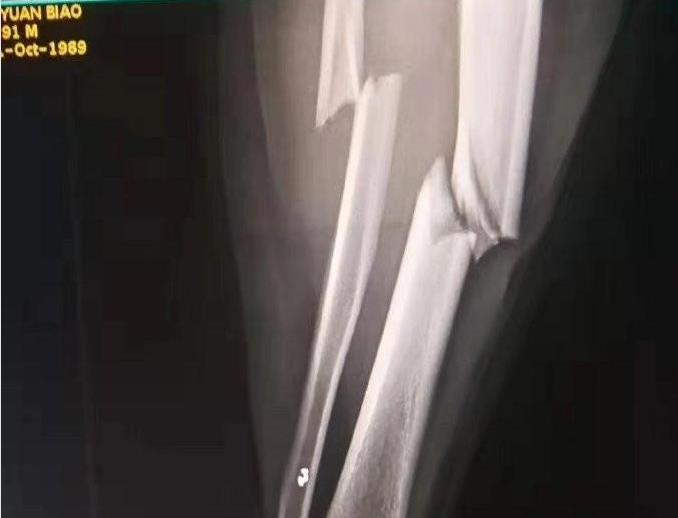

据体育博主“草根足球记录员”介绍,2019年9月5日,韶关西河体育中心足球场,“如美杯”韶关八人足球联赛甲组第四轮,威玛斯东捷一队vs伊盾门窗丞希,下半场55分钟,威玛斯东捷一队以3比1领先伊盾门窗丞希。一队5号队员赵旭将伊盾门窗丞希38号队员郑源标铲离地面,直接导致后者右脚胫腓骨骨折,伤势严重!”

图片来源:微博